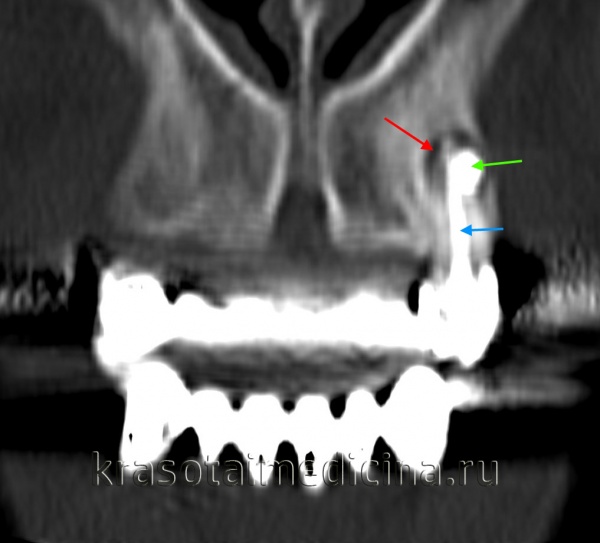

- Рентген ППН. Для исключения прорастания образования в полость придаточных пазух носа необходимо дополнительно провести рентгенографию придаточных пазух. Рентгенологическими признаками кисты служат куполообразное выпячивание и деформация костного дна пазухи. В сомнительных случаях рекомендуется проведение контрастной рентгенографии или компьютерной томографии верхнечелюстной кости.

КТ челюстно-лицевой области. Радикулярная киста (красная стрелка) вблизи корня левого клыка верхней челюсти, состояние после эндодонтического лечения (синяя стрелка – филлер в корневом канале), избыток филлера за пределами верхушки зуба (зеленая стрелка).